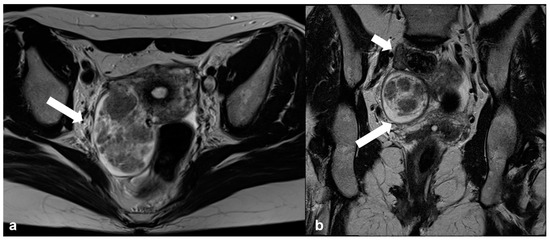

2.3.5. Metastases